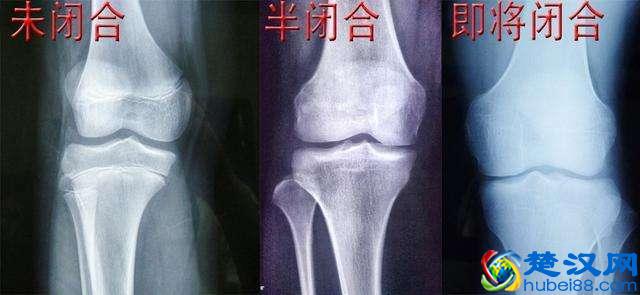

其实,能不能再长高,主要看一个人的骨骺线。指的就是骨骺与干骺端中间的软骨,这个软骨它会因为年龄增长的原因而慢慢骨化,最后变成一条闭合的缝隙,这就是我们所说的骨骺线。

当这个缝隙完全闭合的时候,人的身高也会完全停止生长,如果要看你的骨骺线有无完全闭合,就要去医院拍X光确定。